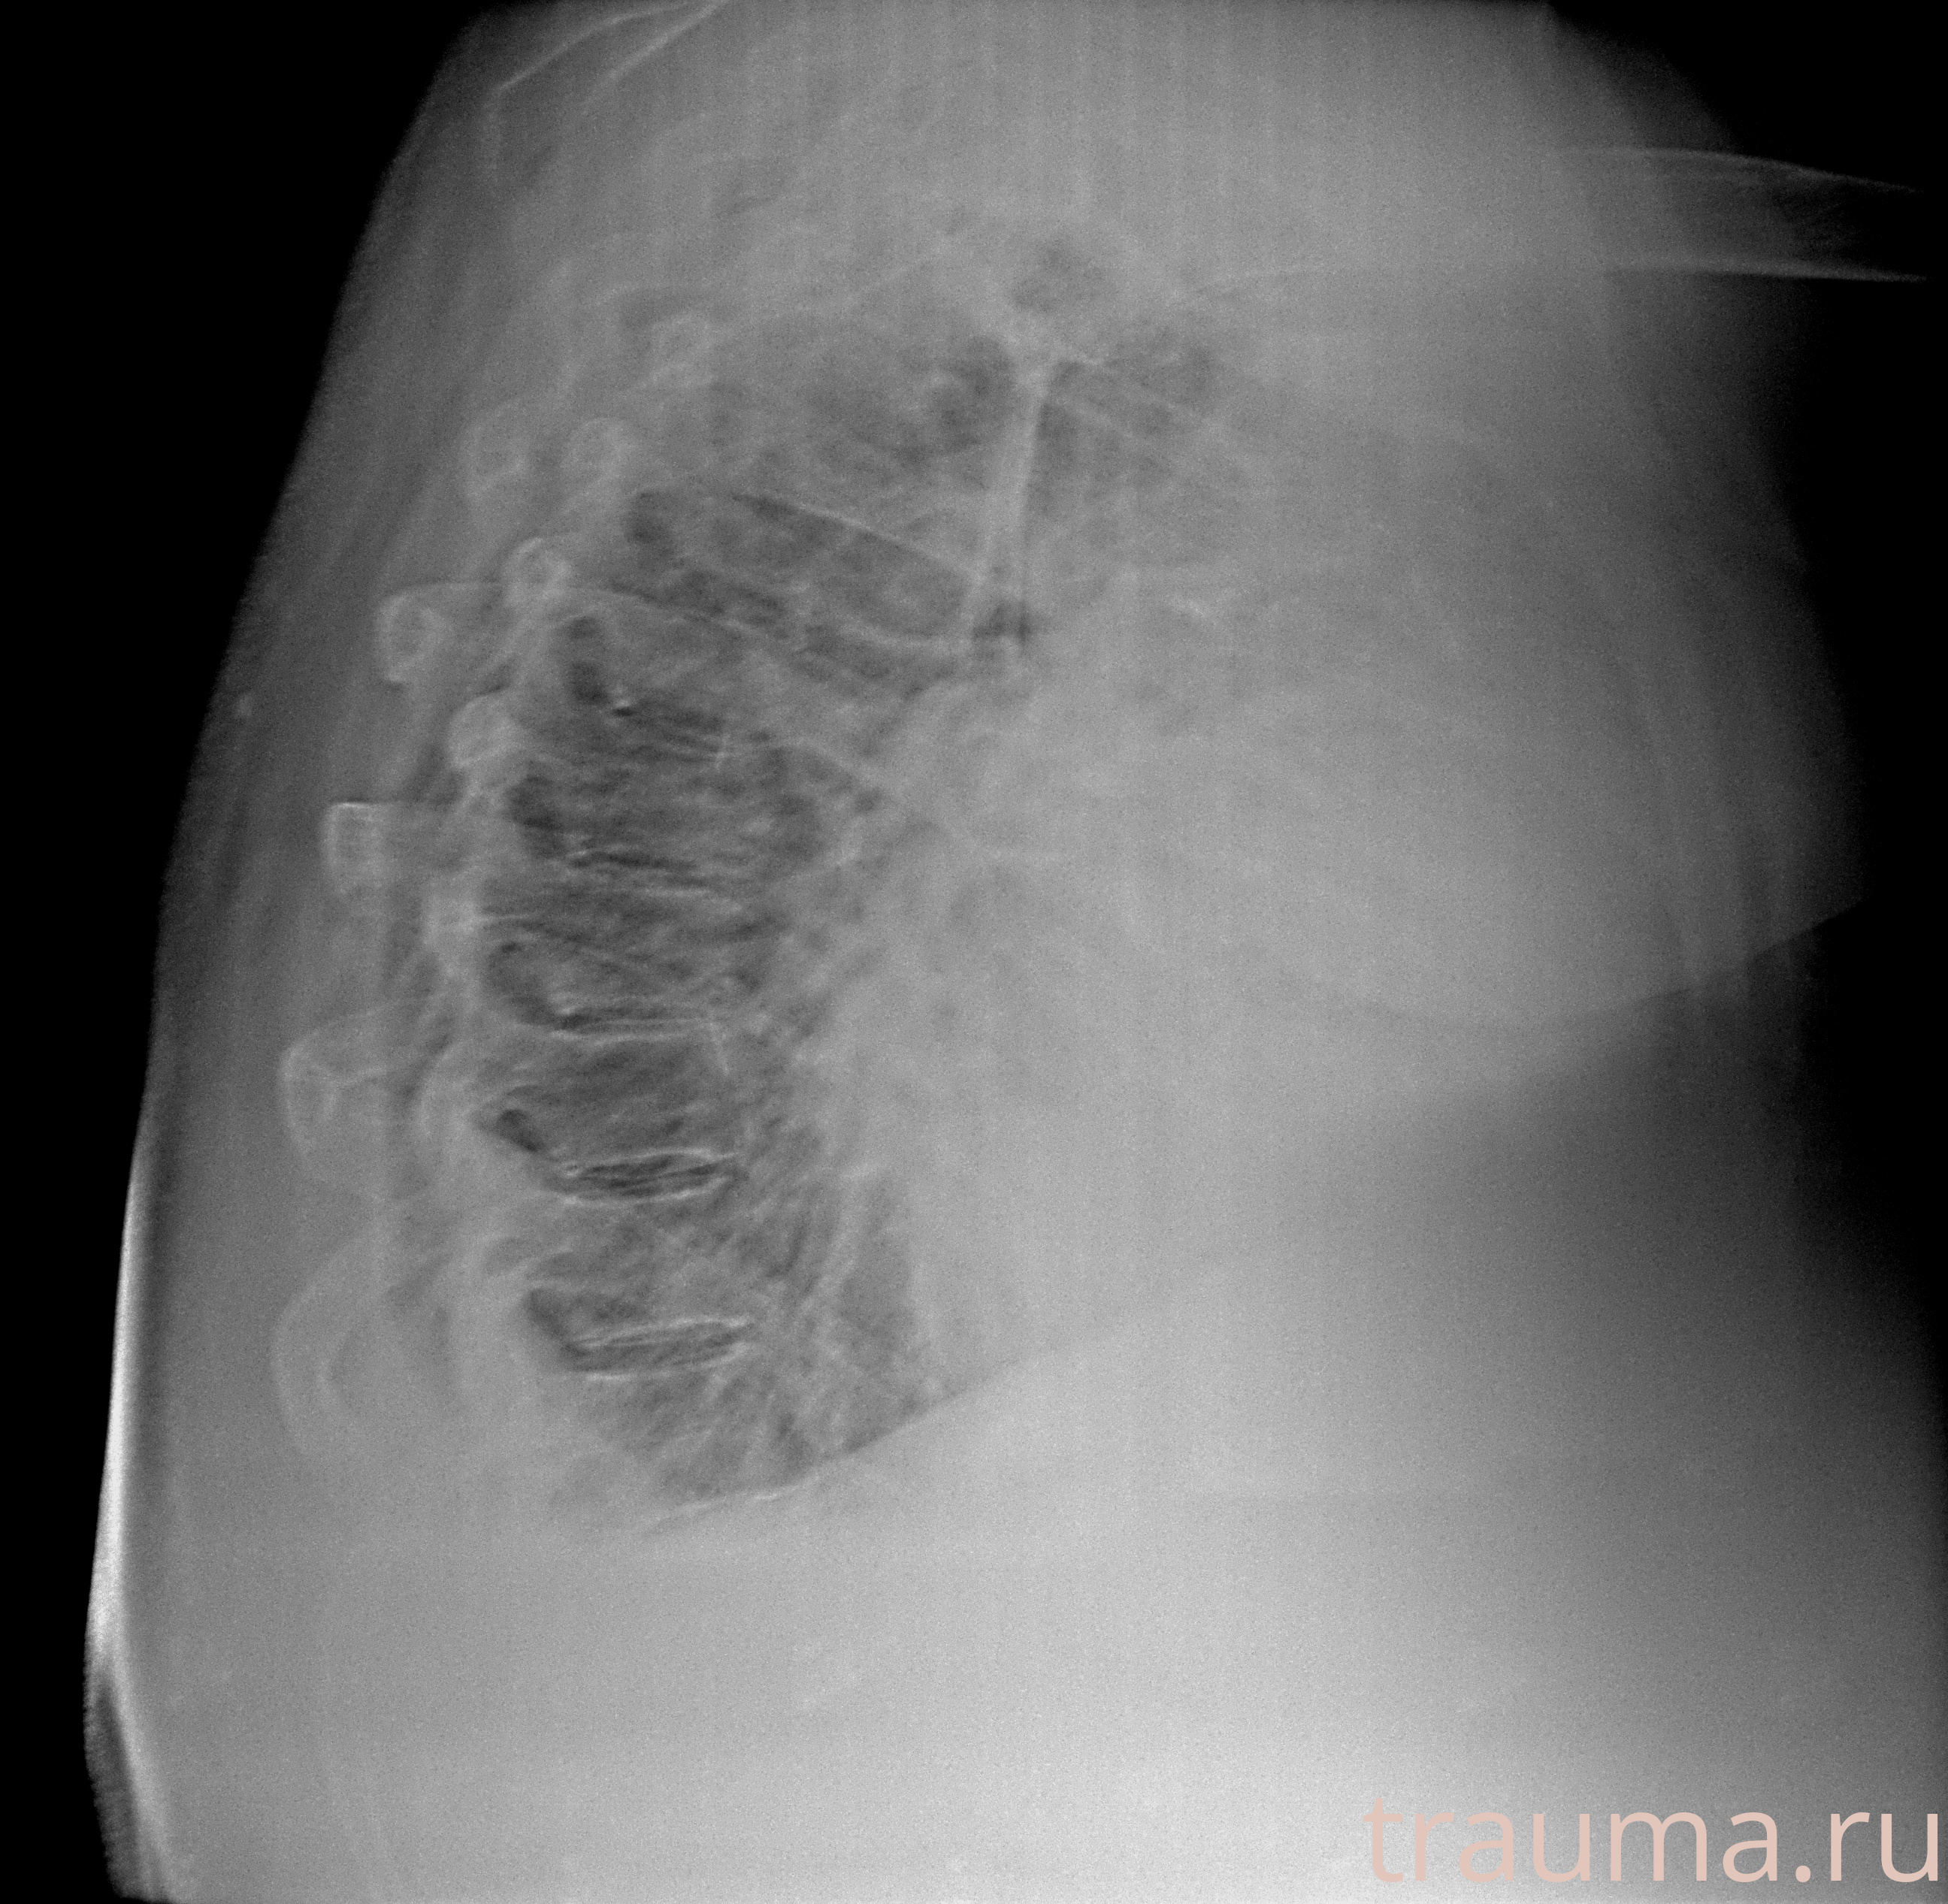

Рентгенограммы

Рентген на дому: по вашему адресу приезжает врач-рентгенолог, травматолог-ортопед с мобильным рентгеновским аппаратом, проводит диагностику травмы или заболевания, делает необходимые рентгенограммы, дает рекомендации по дальнейшему лечению. Получить качественные снимки в домашних условиях возможно благодаря уникальной методике, разработанной МосРентген Центром для института  Склифосовского

при переломе шейки бедра и пневмонии от компании МосРентген Центр - партнера Института имени Склифосовского